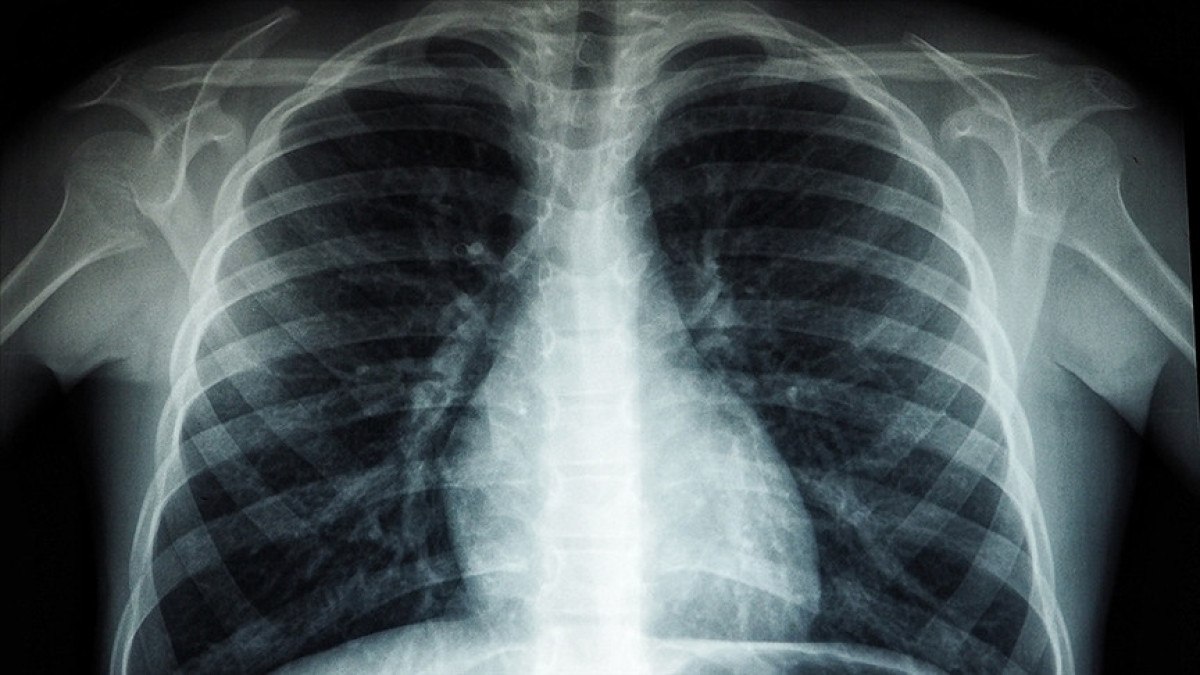

TÜBERKÜLOZ NASIL YAYILIYOR

TB, hasta kişilerin öksürmesi, konuşması veya hatta nefes almasıyla havaya yayılan küçük enfekte damlacıklar aracılığıyla bulaşıyor.